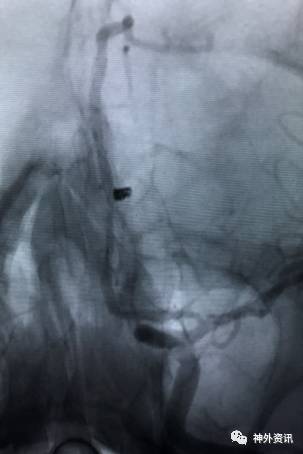

病例一

眼动脉动脉瘤,支架完全释放后,微导管成袢逆行到位